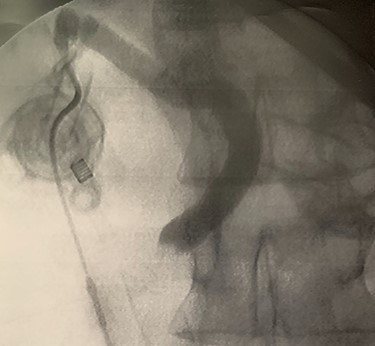

In context of purulent cholangitis, a 10 mm stone was reached (Fig. 4) and extracted with Dormia basket under direct vision (Fig. 5). Furthermore, control choledochoscopy and cholangiography did not show any other stones in the CBD and contrast easily passed into the duodenum (Fig. 6).